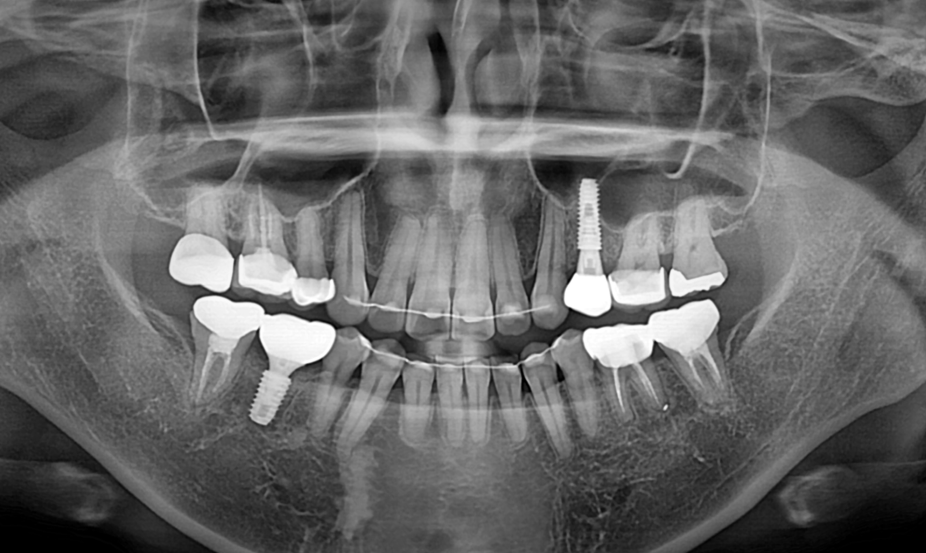

발치 즉시 임플란트.

Before